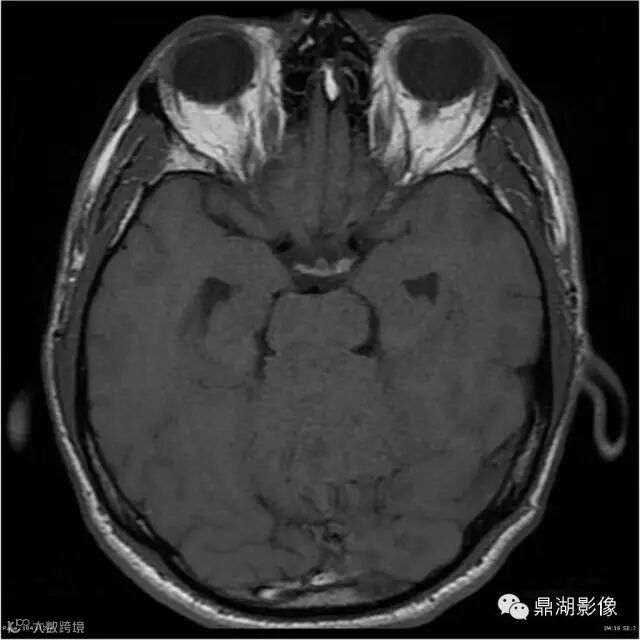

患者男,53岁,头痛、视乳头水肿伴双下肢无力。

影像:可见一个约43 x 36 x 31mm的从小脑蚓部延伸而来的占位,T1WI、T2WI呈高低混杂信号,病灶周边见流空血管影及水肿带,增强病灶明显强化,中心见无明显坏死区,它紧靠左小脑幕上。第四脑室受压变窄,室管膜水肿,可见脑桥及延脑扁桃体进入枕骨大孔。

本例为一例实质性血管母细胞瘤。实性血管母细胞瘤CT平扫示病灶呈等或高密度,增强后可见明显强化。MRI平扫通常病灶很不均质,T1呈稍低信号为主的较混杂信号,T2呈等、高信号,DWI通常呈低信号或等信号。文献报道,实性血管母细胞瘤较典型的表现为瘤内及瘤周扩张的流空血管影,瘤周中、重度水肿。因此,小脑半球区的单发肿块伴流空血管影,周围大片水肿以及增强后肿块明显强化"形态规则"边界清楚,此时应将实性血管母细胞瘤考虑在内。